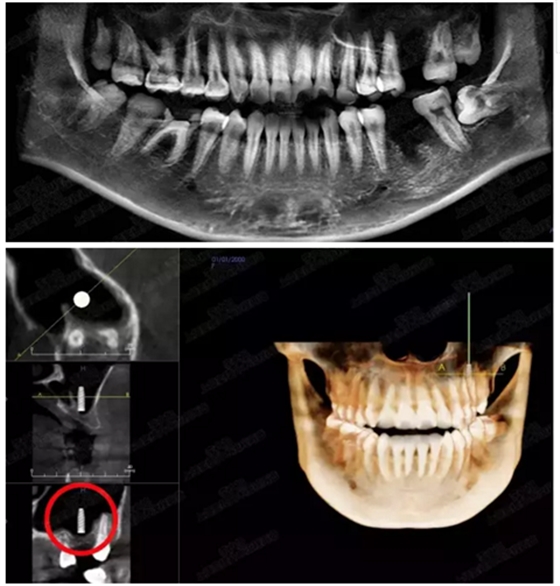

病例一

上頜竇多分隔3mm

05.png

提升8mm

06.png

07.png

修復(fù)時(shí)根尖片

08.png

09.png